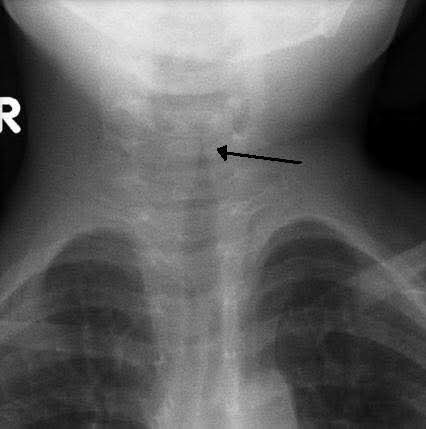

@albertoortegana croup, laryngotracheobronchitis

(Acute laryngeal stenosis)